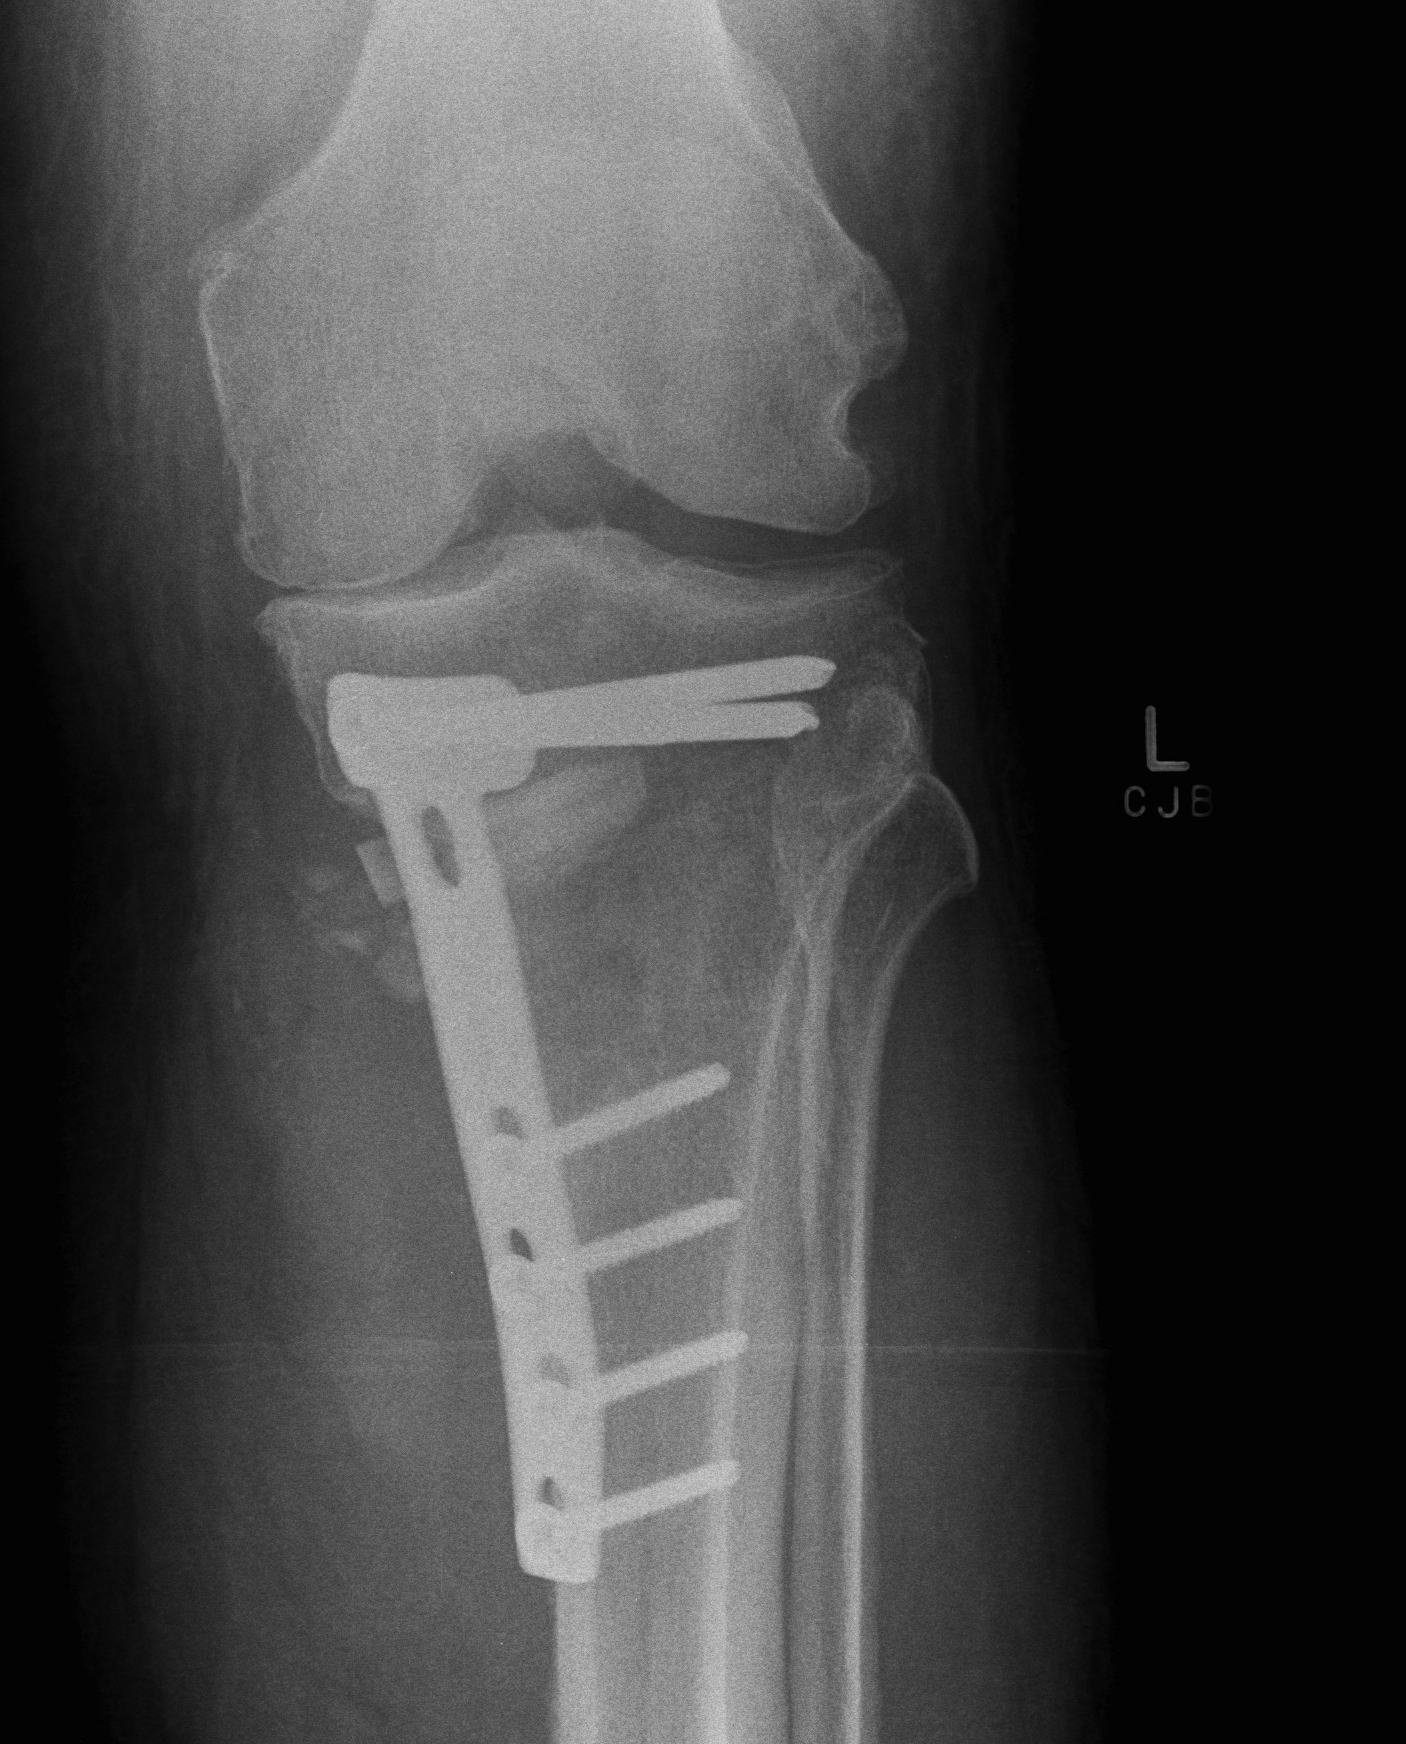

Medial Opening Wedge HTO